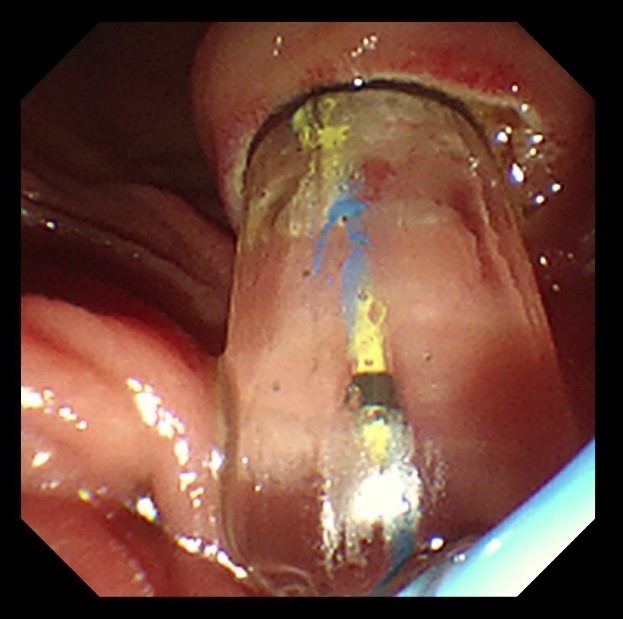

苏大附四院ERCP团队在手术中看到陈大爷的胆总管在结石的影响下已经宽达13mm,结石大小11*10mm,将十二指肠乳头切开并扩张后用取石球囊把结石取出,置入胆管支架使胆汁充分引流,顺利解除了胆道梗阻。

扩张取石